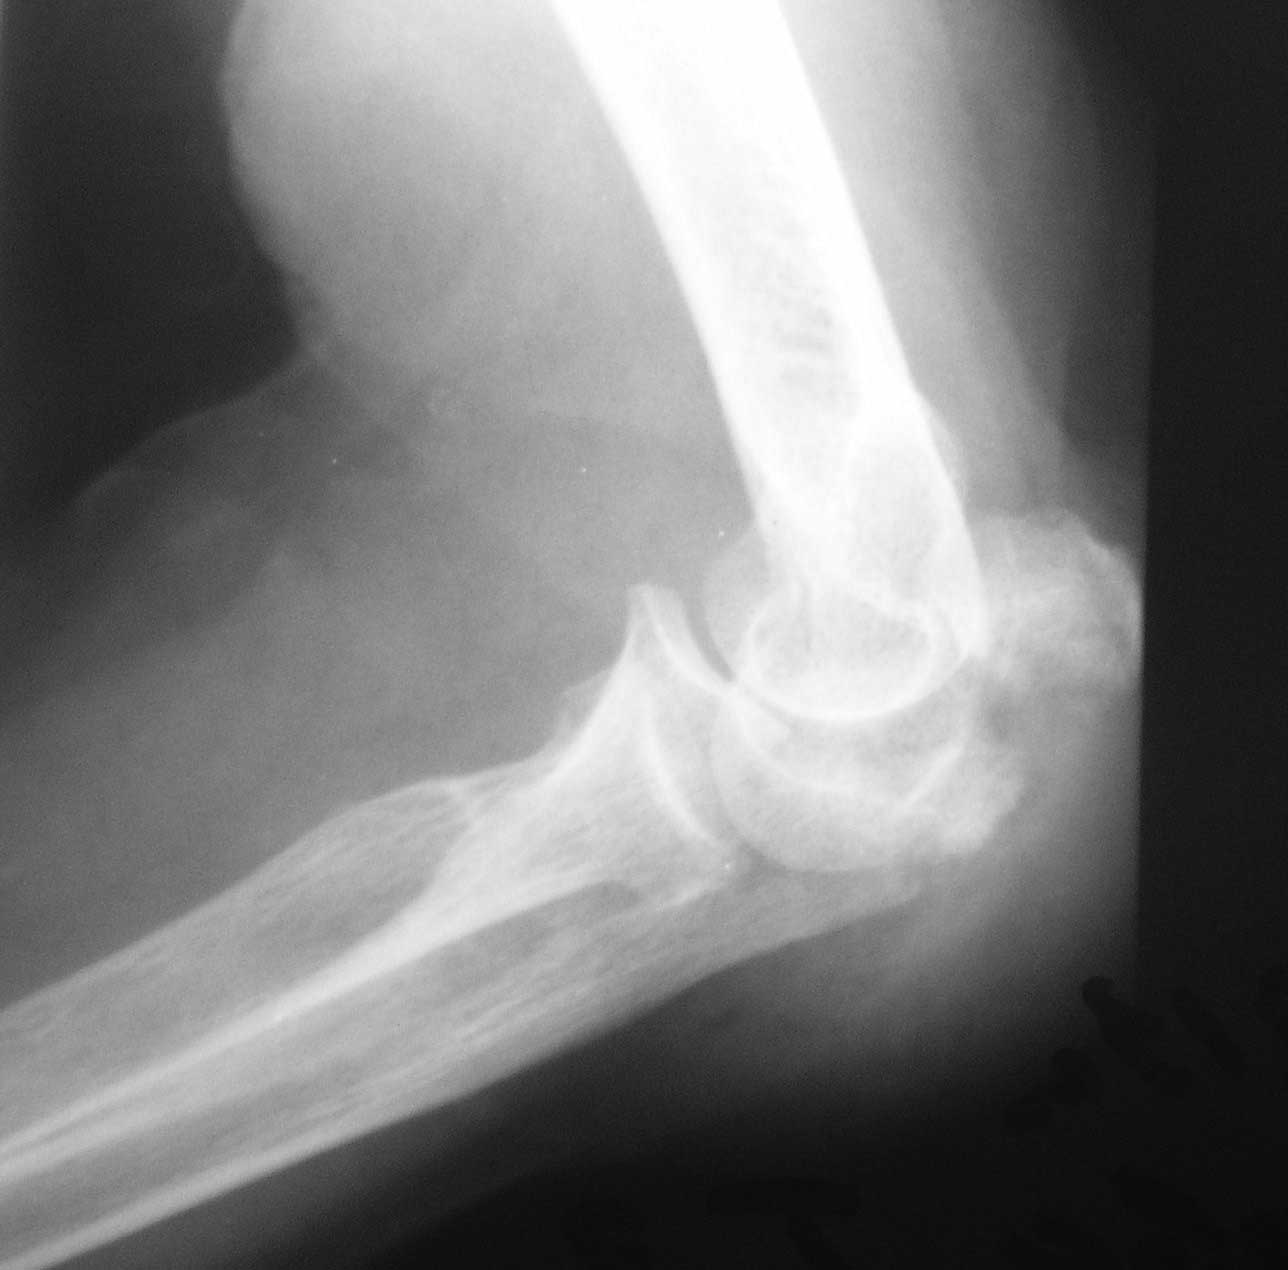

Первоначально на клиническом разборе планировалась костная аутопластика с фиксацией пластинкой или аппаратом внешней фиксации. Однако в течение нескольких дней у больной систематически отмечался подъем АД до 200-220 мм.рт.ст., трудно снимаемый гипотензивной терапией, назначенной по рекомендации терапевта. Через 1 неделю п/травмы больная взята в операционную и … снята со стола с очередным гипертоническим кризом (АД 230/100 мм.рт.ст.). Подключена терапия, на этот раз назначенная кардиологом. Повторное обсуждение случая с врачами отделения. Предложения: или от операции отказаться, или выполнить остеосинтез локтевого отростка, в любом случае - без наркоза. Учитывая «злокачественное» течение гипертонической болезни с исключительно лабильной гемодинамикой в ответ на малейшее эмоциональное волнение пациентки, решено выполнить остеосинтез спицами с проволочной петлей и костной аутотрансплантацией из дистального отломка локтевой кости (из этого же оперативного доступа) под проводниковой анестезией. АД удалось стабилизировать за 2 дня до операции. Через 2 недели после травмы больная вновь взята в операционную. Выполнена верхняя проводниковая анестезия по Соколовскому. Непосредственно перед началом операции на операционном столе у больной опять отмечен подъем АД до 190 мм.рт. ст. . В течение 30 минут анестезиологом проводилась коррекция АД и с давлением 150 мм.рт.ст. операция начата. После выполнения заднего доступа по Фарабефу обнажена зона перелома. Выявлен раздробленный перелом локтевого отростка с множеством промежуточных мелких костных фрагментов и отсутствием губчатой кости (остеопороз), проксимальный отломок представлен 3 –мя отломками размером 1-1,5см каждый, местами связанных между собой надкостницей. В момент ревизии костных отломков АД упало до 100/60 мм.рт. ст. Решено отказаться от выполнения костной аутопластики, и как можно быстрее заканчивать операцию. Произведен остеосинтез локтевого отростка двумя спицами и проволочной петлей, при этом обнаружено, что малейшее стягивание петли, проведенной в виде «обычной восьмерки» ведет к деформации локтевого отростка за счет компрессии (сминания) промежуточных фрагментов. В связи с этим спицы проведены перекрестно друг к другу, а проволока закручена вокруг выстоящих концов спиц (для увеличения стабильности проксимальных отломков), при этом закрученные концы ее не скушены, а уложены вдоль локтевого отростка для предупреждения вторичного смещения промежуточных фрагментов. Продолжительность операции – 35 минут. На контрольных рентгенограммах (доставленных в операционную уже после ушивания раны) – отломки в положении контакта, положение костных отломков локтевой кости удовлетворительное (см. фото 3,4). Гипсовая иммобилизация не проводилась. Правая верхняя конечность подвешена в косыночной повязке.

1) перелом - не оскольчатый, а раздробленный, с повреждением большей части локтевого отростка (С2 по А0, Тип IIIB по Mayo) с явлениями остеопороза, сминания промежуточных костных фрагментов. Подтверждением этому является наличие промежуточных костных фрагментов неопределенной формы, несоответствующей суставной части локтевого отростка, а также хорошо видимый передний подвывих костей предплечья (см. фото 2).